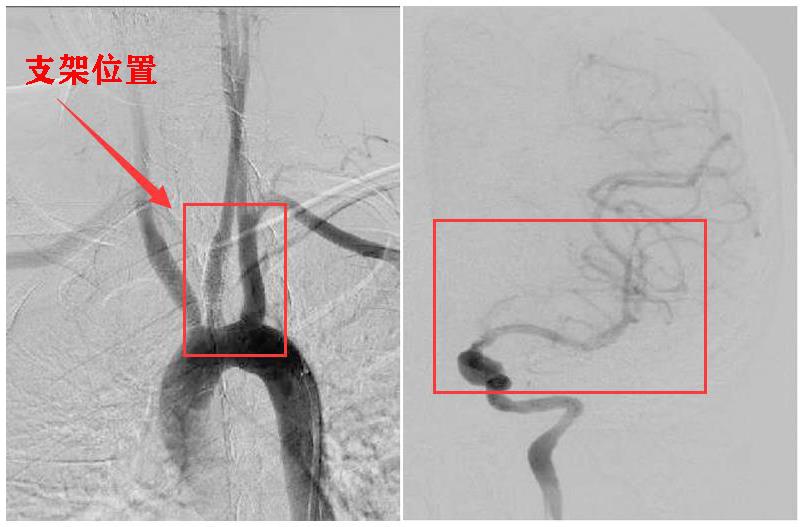

中大五院脑血管病中心主任、神经介入科主任周斌手术团队为她开展手术治疗,术中取出了数枚暗红色血栓,术后患者神经功能缺损评分(分数越高病情越重)由术前的10分降至4分,经过抗血小板、降脂、改善循环等治疗,小云康复出院。

中大五院脑血管病中心主任、神经介入科主任周斌手术团队为她开展手术治疗,术中取出了数枚暗红色血栓,术后患者神经功能缺损评分(分数越高病情越重)由术前的10分降至4分,经过抗血小板、降脂、改善循环等治疗,小云康复出院。